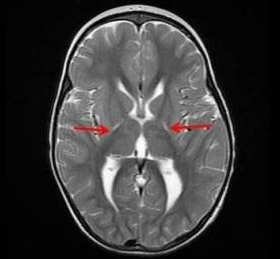

脑瘫(CP)儿童走路有复杂的步态模式和偏差,通常需要物理治(PT)/医学/手术干预。可通过三维仪器步态分析(3D-IGA)进行评估,提供运动学(关节角度)、动力学(关节力矩/功率)和肌肉活动。本文阐述了3D-IGA在外科和非手术干预、识别节段/关节和面之间的步态偏差以及评估干预效果方面的应用。 展开